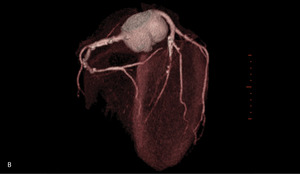

Rycina 1. Badanie tętnic wieńcowych metodą tomografii komputerowej. A. Rekonstrukcja MIP Inwers (maximum intensity projection) – widoczne liczne zwapnienia w lewej tętnicy wieńcowej oraz krytyczne zwężenie w jej środkowym segmencie. B. Rekonstrukcja VR (volume rendering) – krytyczne zwężenie środkowego segmentu lewej tętnicy wieńcowej oraz gałęzi diagonalnej. C. Warstwa poprzeczna (axial) – widoczna blaszka niskiej gęstości wypełniająca światło segmentu środkowego lewej tętnicy wieńcowej.

– Gałąź przednia zstępująca (GPZ): segment 6 z blaszką niskiej gęstości ~30% (remodeling dodatni ściany!); segment 7 – długa blaszka (12-15 mm) niskiej gęstości z remodelingiem dodatnim ściany, zwężająca w części środkowej krytycznie światło ~95%. Referencja proksymalna 4,3 mm, dystalna 2,1 mm; segment 7 za zmianą i segment 8 z wielopoziomowymi blaszkami niskiej gęstości ~30% (ryc. 1).